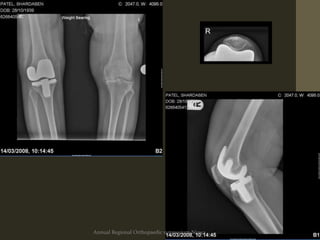

Diagnosis: Radiological

• Early Lysis/Lucencies

• Progressivelucent

lines

• Lytic area(s)

• Prosthesis position

• Stem movement

• Cortical perforation